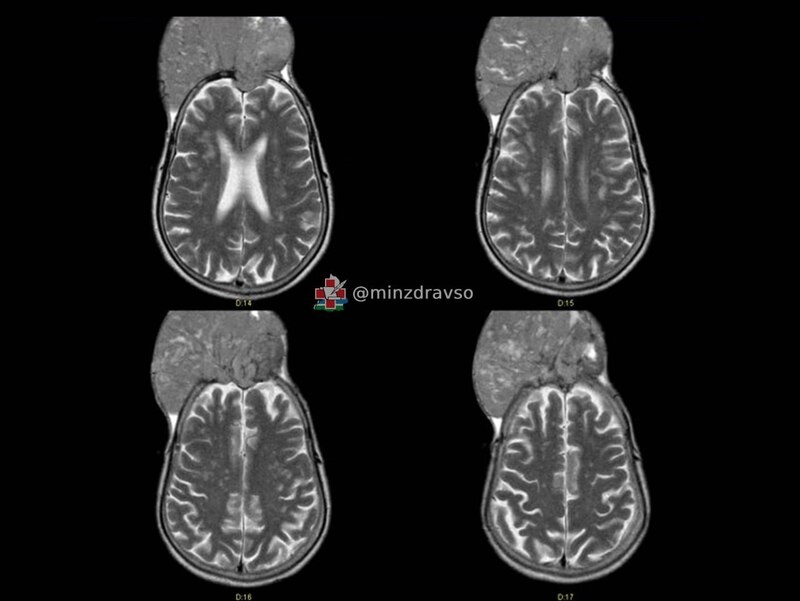

В Свердловской области нейрохирурги онкодиспансера спасли жителя Краснотурьинска. Мужчина поступил к ним с огромной менингиомой, которая в буквальном смысле начала поглощать его череп. Она проросла кости черепа и распространилась наружу на 10 сантиметров. «На вопрос, почему пациент так долго не обращался к врачам, хотя «вторая голова» росла буквально на глазах, мужчина ответить затруднился. В итоге новообразование достигло размеров примерно 15 на 15 сантиметров», — отметил Павел Гвоздев, нейрохирург Свердловского областного онкодиспансера. Эта опухоль хоть и является доброкачественной, но она может лишить человека слуха, зрения, речи, чувствительности и возможности двигаться. Поэтому, как сообщили в Минздраве Свердловской области, было решено проводить операцию. В ходе её первого этапа нейрохирурги «закупорили» нужные сосуды, после чего отделили менингиому от головного мозга, установили титановую сетку, выполнили пластику и другие манипуляции, для формирования правильной формы черепа.

В Свердловской области нейрохирурги онкодиспансера спасли жителя Краснотурьинска. Мужчина поступил к ним с огромной менингиомой, которая в буквальном смысле начала поглощать его череп. Она проросла кости черепа и распространилась наружу на 10 сантиметров.

«На вопрос, почему пациент так долго не обращался к врачам, хотя «вторая голова» росла буквально на глазах, мужчина ответить затруднился. В итоге новообразование достигло размеров примерно 15 на 15 сантиметров», — отметил Павел Гвоздев, нейрохирург Свердловского областного онкодиспансера.

Эта опухоль хоть и является доброкачественной, но она может лишить человека слуха, зрения, речи, чувствительности и возможности двигаться. Поэтому, как сообщили в Минздраве Свердловской области, было решено проводить операцию.

В ходе её первого этапа нейрохирурги «закупорили» нужные сосуды, после чего отделили менингиому от головного мозга, установили титановую сетку, выполнили пластику и другие манипуляции, для формирования правильной формы черепа. Операция по спасению жителя Краснотурьинска длилась 7 часов и завершилась благополучно. При этом хирурги удалили мужчине участок кожи с облысением. Поэтому мужчина не лишился возможности носить красивую прическу.